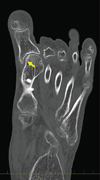

Three-dimensional computed tomography (3DCT) revealed the hallux varus deformity and dorsal dislocation of the second toe (Figure 2(a)). Osteophyte formation was observed at the proximal end of the phalanx. On the coronal image, the surface area of the medial side of the articular surface at the first metatarsal head was decreased by the resection of the bony prominence (Figure 2(b)). Because her symptoms such as pain and gait disturbance had worsened, surgery was performed.

(a)

(b)

(c)